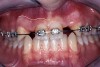

Periapical radiographs were taken to help determine the mesial-distal inclinations of the adjacent tooth roots (Figure 1). The radiographs revealed a serious issue, convergent roots for the right canine and right central, which eliminated that area as a potential implant-receptor site. The space between the left central and canine teeth was minimal, although the roots were relatively parallel. Clinical examination (manual palpation of the root eminences superiorly to the vestibule on the right side) confirmed the root convergence (Figure 2A). The flat, wide zone of the keratinized tissue and lack of interdental papilla was evident for the missing right lateral incisor. There was a marked difference in clinical appearance for the left lateral, which could impact the eventual plan of treatment (Figure 2B). Other significant clinical findings included bilateral facial bone concavities, which existed as a result of the congenitally missing tooth roots. As a diagnostic cue to the underlying bone topography, it is important to follow the demarcation between attached and unattached gingival tissue, and note the crestal width of the available keratinized tissue (Figure 2C).

Figure 1  Pretreatment radiographs revealed convergent roots for the right canine and right central.

Figure 1

Figure 2a  Pretreatment buccal views showed (A) root convergence, (B) a difference in clinical appearance of the left lateral, and (C) significant crestal width of keratinized tissue.

Figure 2a